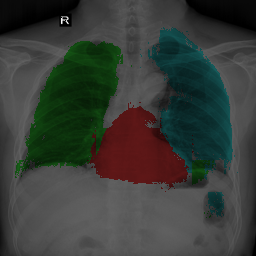

To bridge the methodological gaps when only small-scale partially labeled data is available, we propose a simple yet efficient framework Vicinal Labels Under Uncertainty (VLUU) by exploring the statistical similarity of human structures (e.g. shape, size, location) among different patients. See Fig. 1 for an illustration of such a similarity. The proposed framework is motivated by vicinal risk minimization (VRM) [11], where the fully labeled vicinal examples are generated by linearly combining randomly sampled partial labels with a weight randomly sampled from a Dirichlet distribution. These vicinal examples allow us to transform the partially supervised problem into a fully supervised one. That is to say, we can utilize any existing supervised segmentation networks and loss functions to solve partially supervised problems. The generated vicinal labels contain uncertainty regions where classes of interest could potentially overlap. We utilize these uncertainties in the training process to improve the robustness of DL models.

In standard adversarial training, the segmentation network and the discriminator play a zero-sum game. The discriminator is trained to discriminate the prediction masks produced by the segmentation network from the ground truth masks. Meanwhile, the segmentation network is trained to confuse the discriminator by producing realistic prediction masks. Adversarial training benefits from the human structure similarity as it makes the unknown true label distributions easier to be caught by the discriminator than for general objects [38]. In other words, there is smaller instance-wise variation in the size, shape, and location of human organs (or structures), as shown in Fig. 1, than for general objects.